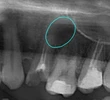

Diş Ağrısı

Diş Çürükleri

Diş Eksikliği

Diş ve Diş eti hastalıkları

Çene Kistleri

Implant tedavisi